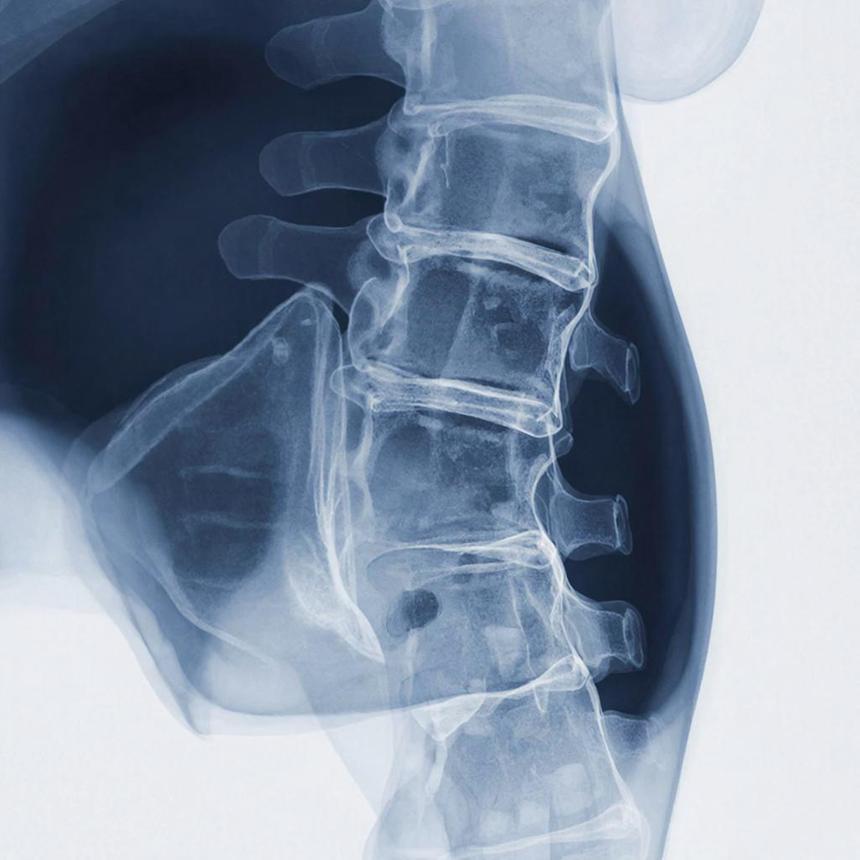

Сферические кластеры (сфероиды) смешивали с β-трикальцийфосфатом. Затем эту смесь транспортировали к позвонкам L4 и L5 у крыс с переломами позвоночника. Причиной же переломов стал остеопороз.

У группы крыс, которую лечили остеогенными сфероидами, значительно увеличилась костная масса, улучшились показатели сращения и механическая прочность. Согласно гистологическому анализу, происходило усиленное образование новой костной ткани, интеграция β-трикальцийфосфата.